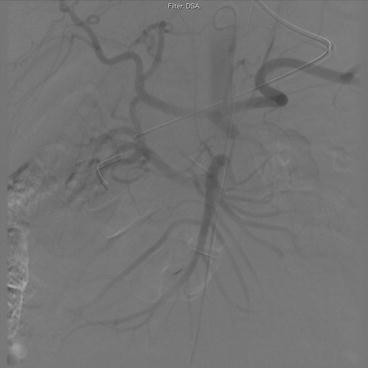

Balloon fenestration of the descending aortic flap. Vascular access was obtained via the right common femoral artery. The right renal artery was first engaged and the pressure was 50 mmHg lower than in the proximal aorta, with a mean pressure gradient of 22 mmHg. The vessel itself was patent on selective right renal artery injection. Intravascular ultrasound (IVUS) of the aortic true lumen showed it to be severely compressed in the suprarenal segment with a dynamic component. Using a 6 F Pioneer® Plus catheter (Medtronic CardioVascular, Santa Rosa, CA) a puncture was made from the true lumen to the false lumen during visualization with IVUS. A coronary wire was advanced into the false lumen all the way to the origin of the left subclavian artery where it stopped. Fenestration with 10 and 14 mm balloons followed (Movie 1). Repeat IVUS of the true lumen showed it to be markedly expanded and a large gap in the flap just below the origin of the renal artery was visualized. IVUS of the right renal artery showed it to be patent. Repeat measurement of pressure in the renal artery showed that the mean gradient had decreased to 16 mmHg. Normal flow was seen in the celiac and mesenteric arteries after fenestration (Panel A)